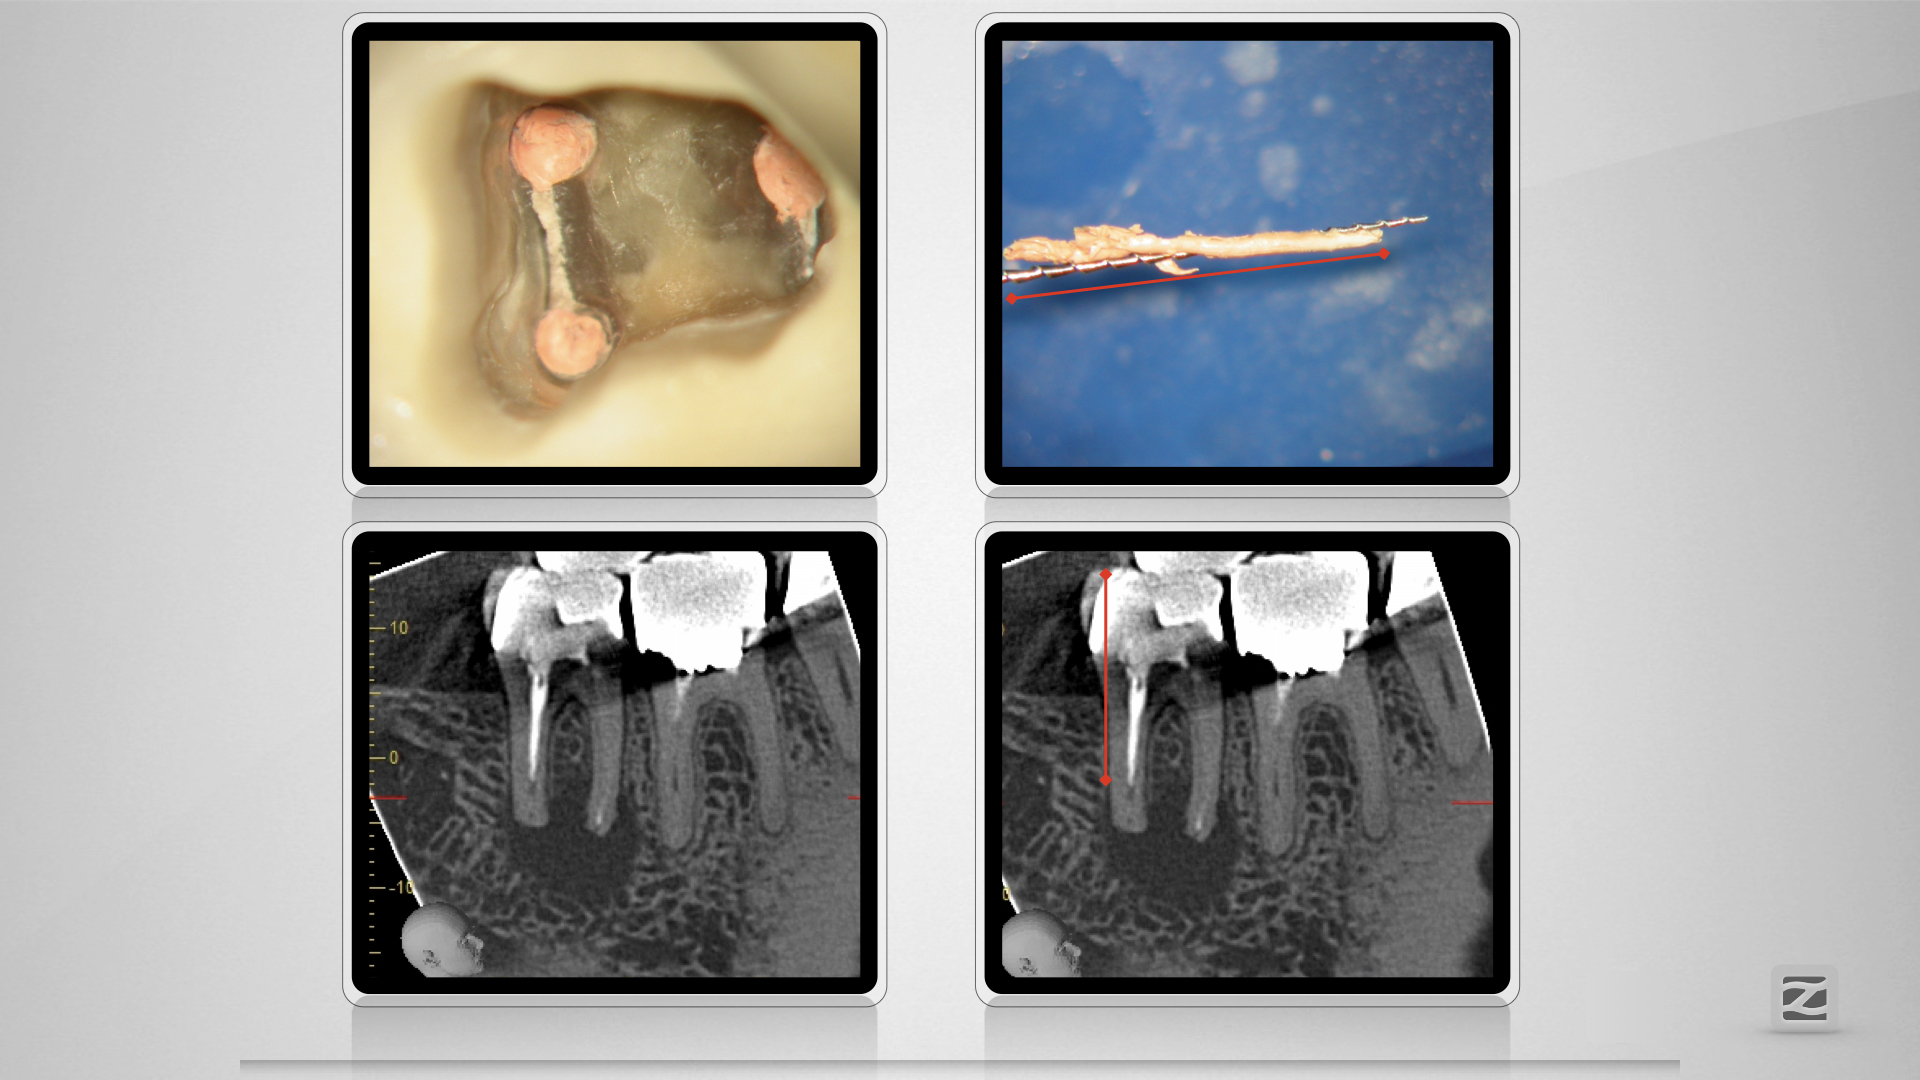

47D.006

Kuhfuß